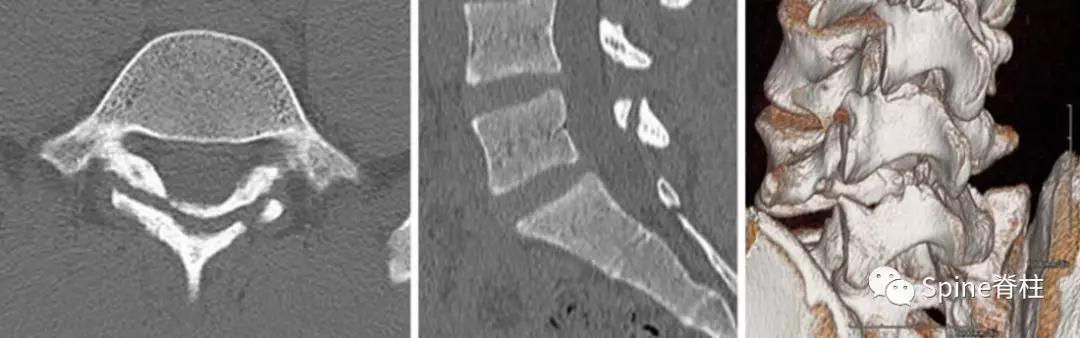

随后,Sairyo教授进一步CT研究,将Morita分型早期又分为 最早期 (very early): 骨折线模糊或不连续的骨折线和 晚早期 (late-early): 骨折线清晰明显。

图:腰5双侧峡部裂,右侧为 最早期 ,左侧为 晚早期

- 峡部裂的Kaneko分型:

图:Kaneko分型

a为 完全骨折 ,b为 不完全骨折

c为 骨折前期 :峡部皮质骨可见放射缺损区